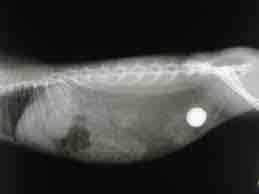

Radiographie abdominale:

Pour la recherche de pathologies concernant les organes abdominaux (foie, reins, rate, appareil digestif…)